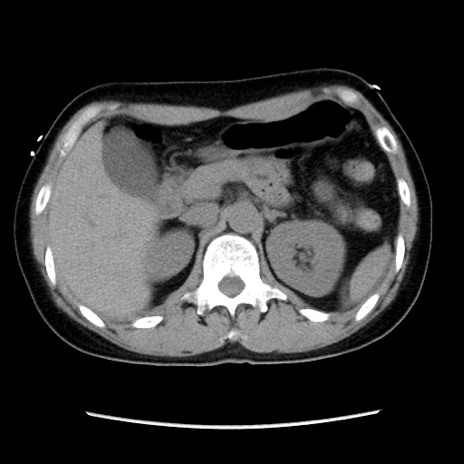

症例10(横断像)

【症例】 50歳代女性

【主訴】 腹痛

【現病歴】前日生レバーを食べた。今朝に排便あり。 昼前に突然発症の腹痛を生じ、当院救急外来を受診した。

【身体所見】 意識清明、腹部:平坦、軟、下腹部やや左を中心に圧痛・反跳痛あり、筋性防御あり

【データ】WBC 7800、CRP 0.07